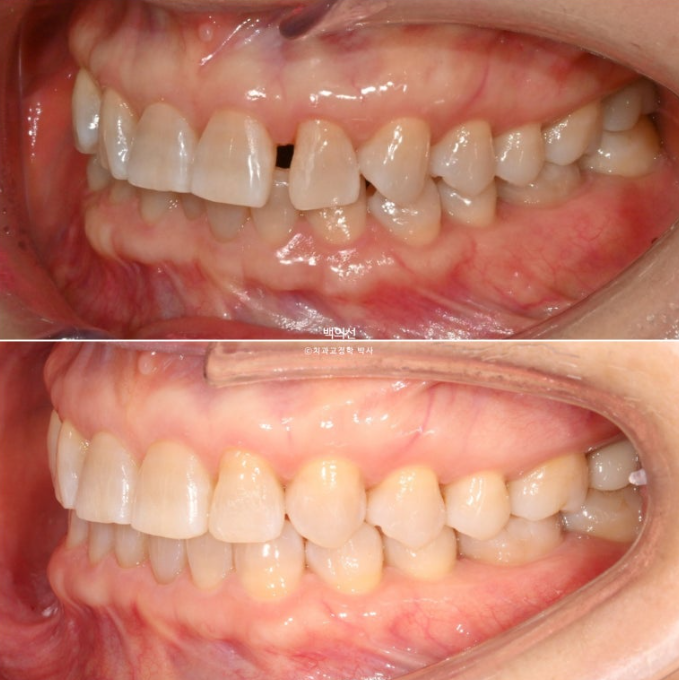

25.02

앞니가 깊게 물리는 과개교합이 보입니다.

파란 화살표는 벌어진 틈을 레진으로 메꿔놓은 곳 입니다.

레진 치료를 감쪽같이 잘 해놓으셨습니다.

앞니의 뻗침이 있습니다.

파란 화살표는 틈을 메워놓은 레진 입니다.

2월부터 4월까지 두 달간 장치를 다 낀 후 모습입니다.

25.04

벌어져 있던 큰 틈은 사라졌고 앞니 뻗침은 개선이 되었습니다.

그러나 앞니 사이사이 치실이 헐렁하게 들어갈 정도의 미세한 틈은 남아있는 상태입니다.

재제작이 필요합니다.

아래 앞니 배열은 벌써 가지런해졌습니다.